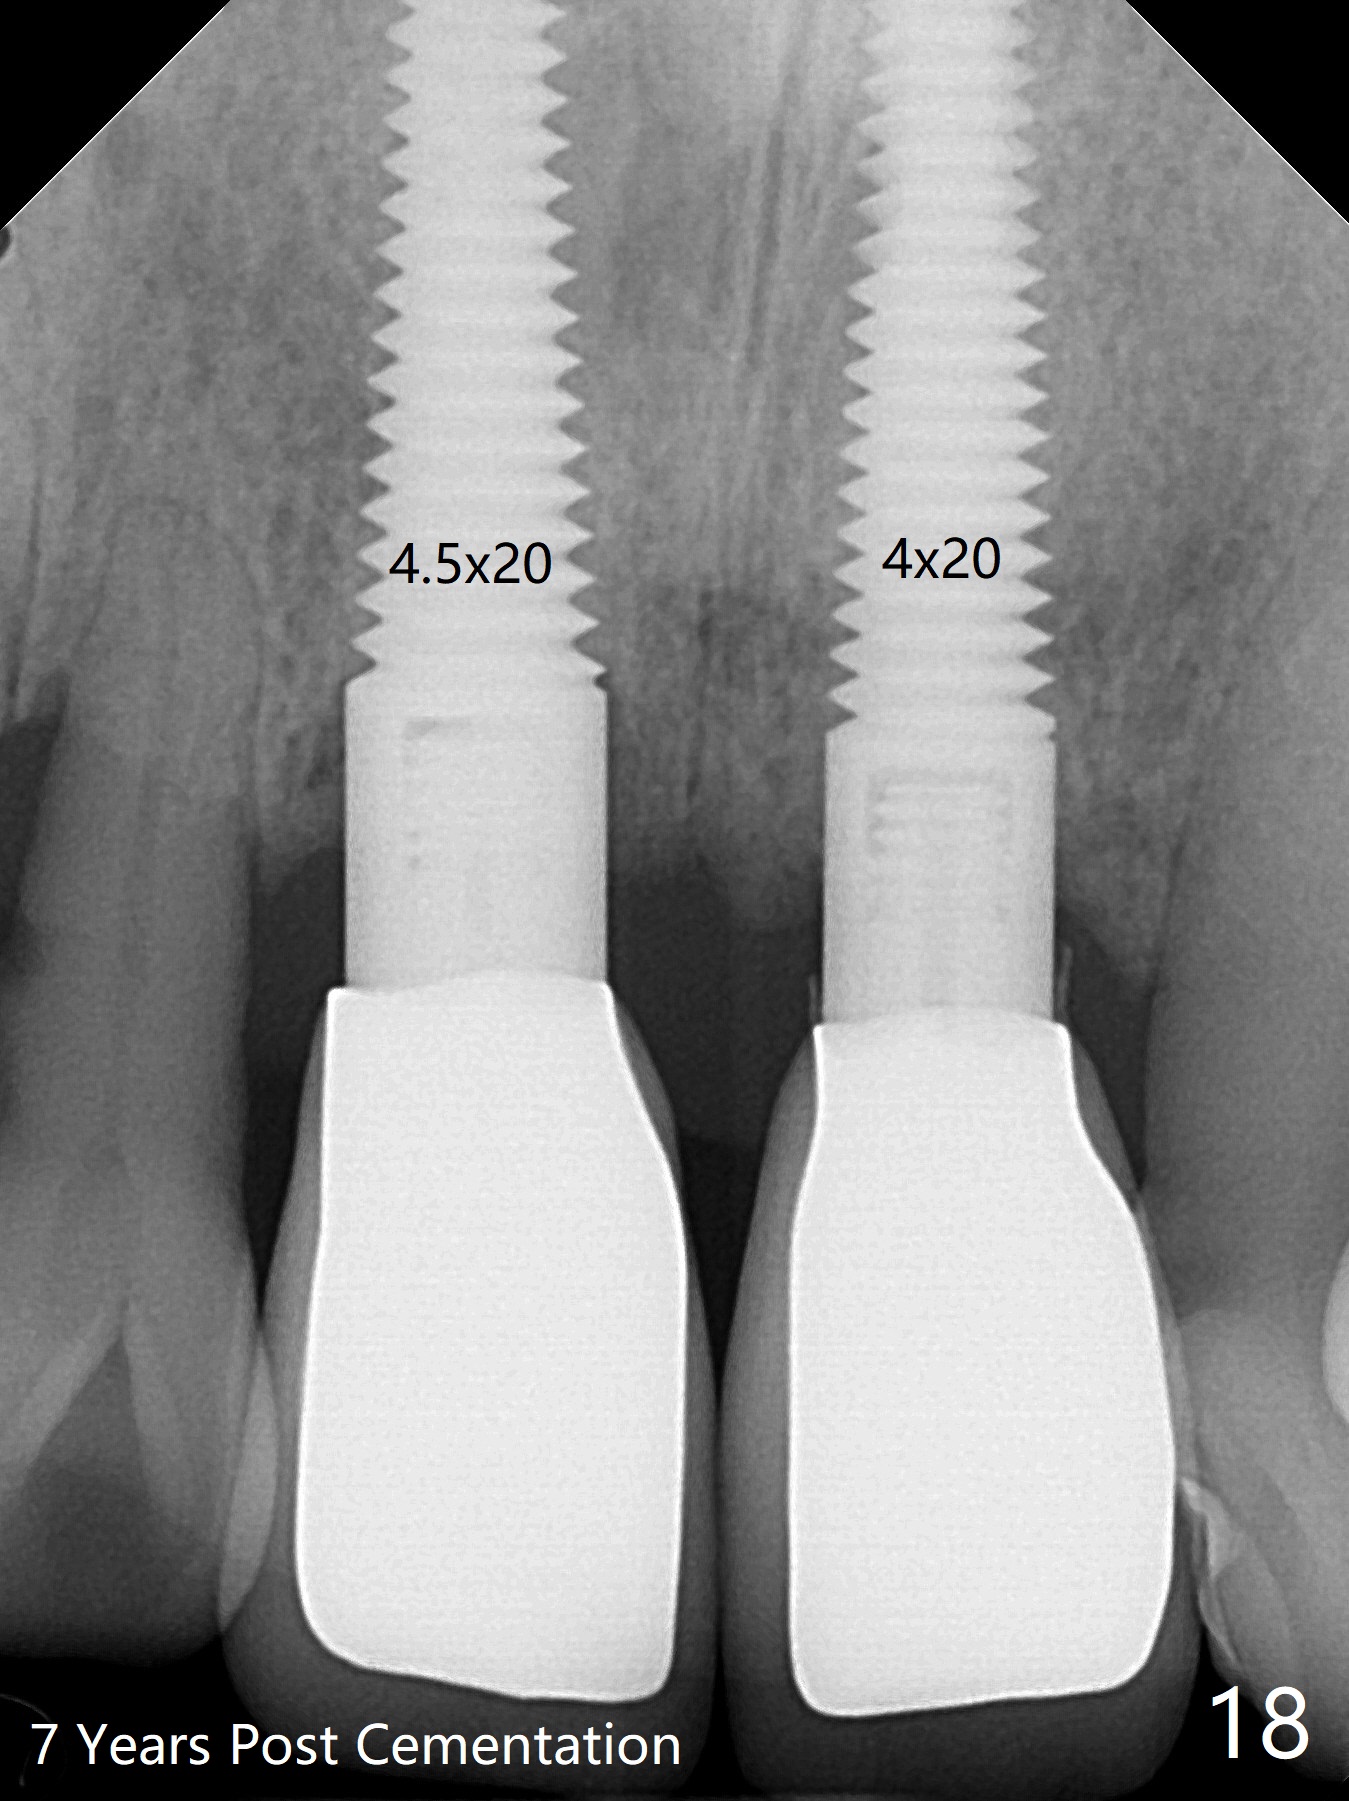

The insertion torque for the implants (4.5x20 mm and 4x20 mm) are 40 and 60 Ncm for #8 and 9, respectively (Fig.7). The stability is probably due to the fact that these two implants are engaged into the two cortical plates of the sockets (arrowheads). Allograft is placed in the mesiodens sockets. Immediate provisionals are fabricated. Fig.8,9 show the provisionals 18 days postop. One of the provisionals (#8) is dislodged 5 weeks postop. Before recementation of the provisional (Fig.10), healthy granulation tissue is found next to the implant (^).

These two anterior implants remain stable 2 months 20 days postop, since one of the immediate provisionals has incisal chip (Fig.11 *) while both of them are splinted (<) to increase retention. There is no complain about paresthesia around the incisal papilla due to separation of the nasopalatine nerve. Mesiodens sockets disappear 7 months postop (Fig.13). There is no bone loss 2 years 9 months postop (Fig.14 panoramus) or 4 years 10 months postop (Fig.15,16 CT). The buccal gingiva is reddish and swollen with bleed on probing and history of pain 7 years post cementation (Fig.17). There is no bone loss in PA (Fig.18). The buccal plate at #9 is thinner than that at #8 4 years 10 months post cementation (Fig.19,20).